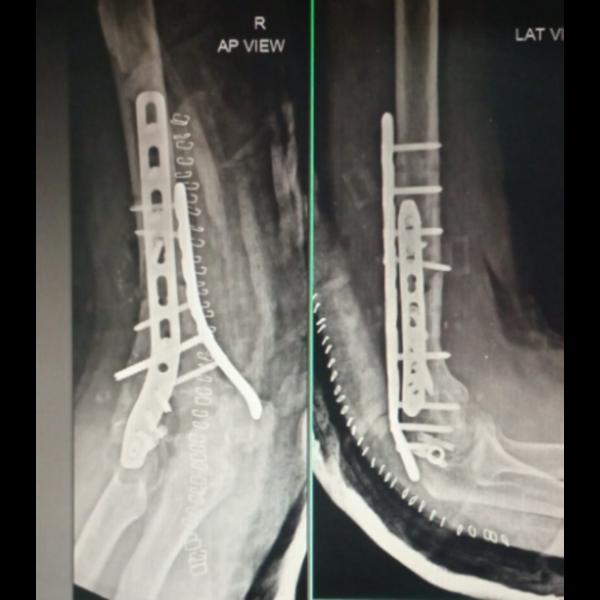

Non union of distal femur intraarticular fracture with implant failure operated elsewhere !